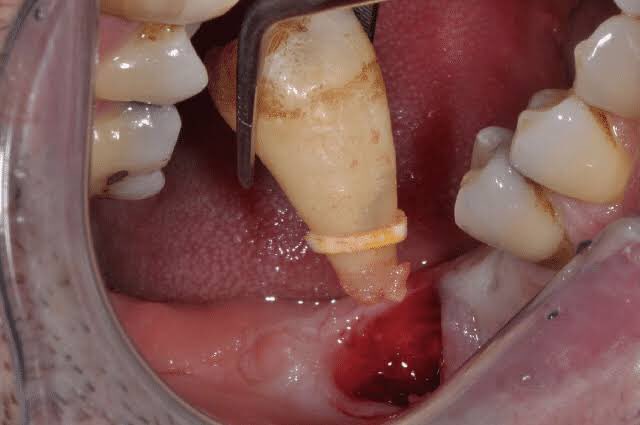

Đây là nỗi sợ lớn nhất khiến nhiều người trì hoãn. Tuy nhiên, tại Nha khoa Lạc Việt Intech, nhờ công nghệ hiện đại và tay nghề bác sĩ, việc nhổ răng khôn diễn ra nhanh, nhẹ nhàng và an toàn.

Nhổ răng khôn không gây đau như mọi người vẫn nghĩ, nếu được thực hiện nhờ công nghệ hiện đại và tay nghề bác sĩ giỏi.

• Chụp phim CT ConeBeam 3D: Cho phép bác sĩ đánh giá chính xác hướng mọc, vị trí dây thần kinh và các cấu trúc quan trọng.

• Lập kế hoạch phẫu thuật: Giúp hạn chế tối đa sang chấn, tổn thương.

• Gây tê hiện đại: Kiểm soát đau tốt, giúp bệnh nhân thoải mái trong suốt quá trình nhổ.

• Sử dụng máy siêu âm Piezotome: Giúp tách dây chằng một cách nhẹ nhàng, hạn chế tổn thương mô mềm.

Thông thường, bệnh nhân chỉ hơi khó chịu trong 1-2 ngày đầu, sau đó ăn uống, sinh hoạt bình thường. Những lo lắng thường gặp như méo miệng hay biến chứng thần kinh cũng được kiểm soát tốt nhờ kỹ thuật chụp phim 3D hiện đại, giúp bác sĩ tránh vùng nguy hiểm.